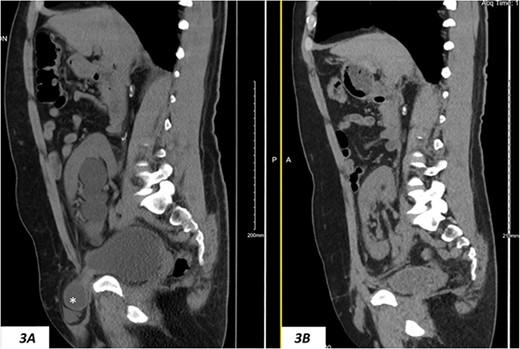

Despite a new onset proteinuria of 50 mg/dl, he continued to have a good functioning graft with a creatinine level of 93 μmol/l corresponding to an estimated glomerular filtration rate (eGFR) of 78 ml/min/1.73 m2. Nonetheless, he had also been noting an inguinal bugle that becomes more prominent as the day progressed, and it regressed at night. Upon further investigations, an ultrasound of the allograft revealed moderate-to-severe hydronephrosis. Further imaging using computed tomography scan (CT) confirmed the presence of upstream moderate hydronephrosis (Figs 1A and2A) along with a reported herniation of the ureter in a right inguinal hernia, resulting in a focal distal ureteric dilatation of 3.5 cm (Fig. 3A).

(A) Hydronephrosis of the allograft ureter on preoperative coronal CT scan; (B) significant improvement of hydronephrosis on the 10-month postoperative image.

(A) Hydronephrosis on preoperative sagittal CT scan showing the reported dilated part of the distal ureter (*), which was correctly identified intraoperatively as a sliding dome of the bladder; note the relationship to the pubic bone; (B) significant improvement of hydronephrosis on the 10-month postoperative image.

The hydronephrosis significantly improved in the 1-year follow-up imaging (Figs 1–3B). The patient continues to enjoy satisfactory graft function with no hernia recurrence. As of July 2023, the patient had further improvement in graft function reflected via a serum creatinine of 76 μmol/l reflecting a eGFR of 99 ml/min/1.73 m2 and 10 mg/dl of proteinuria.